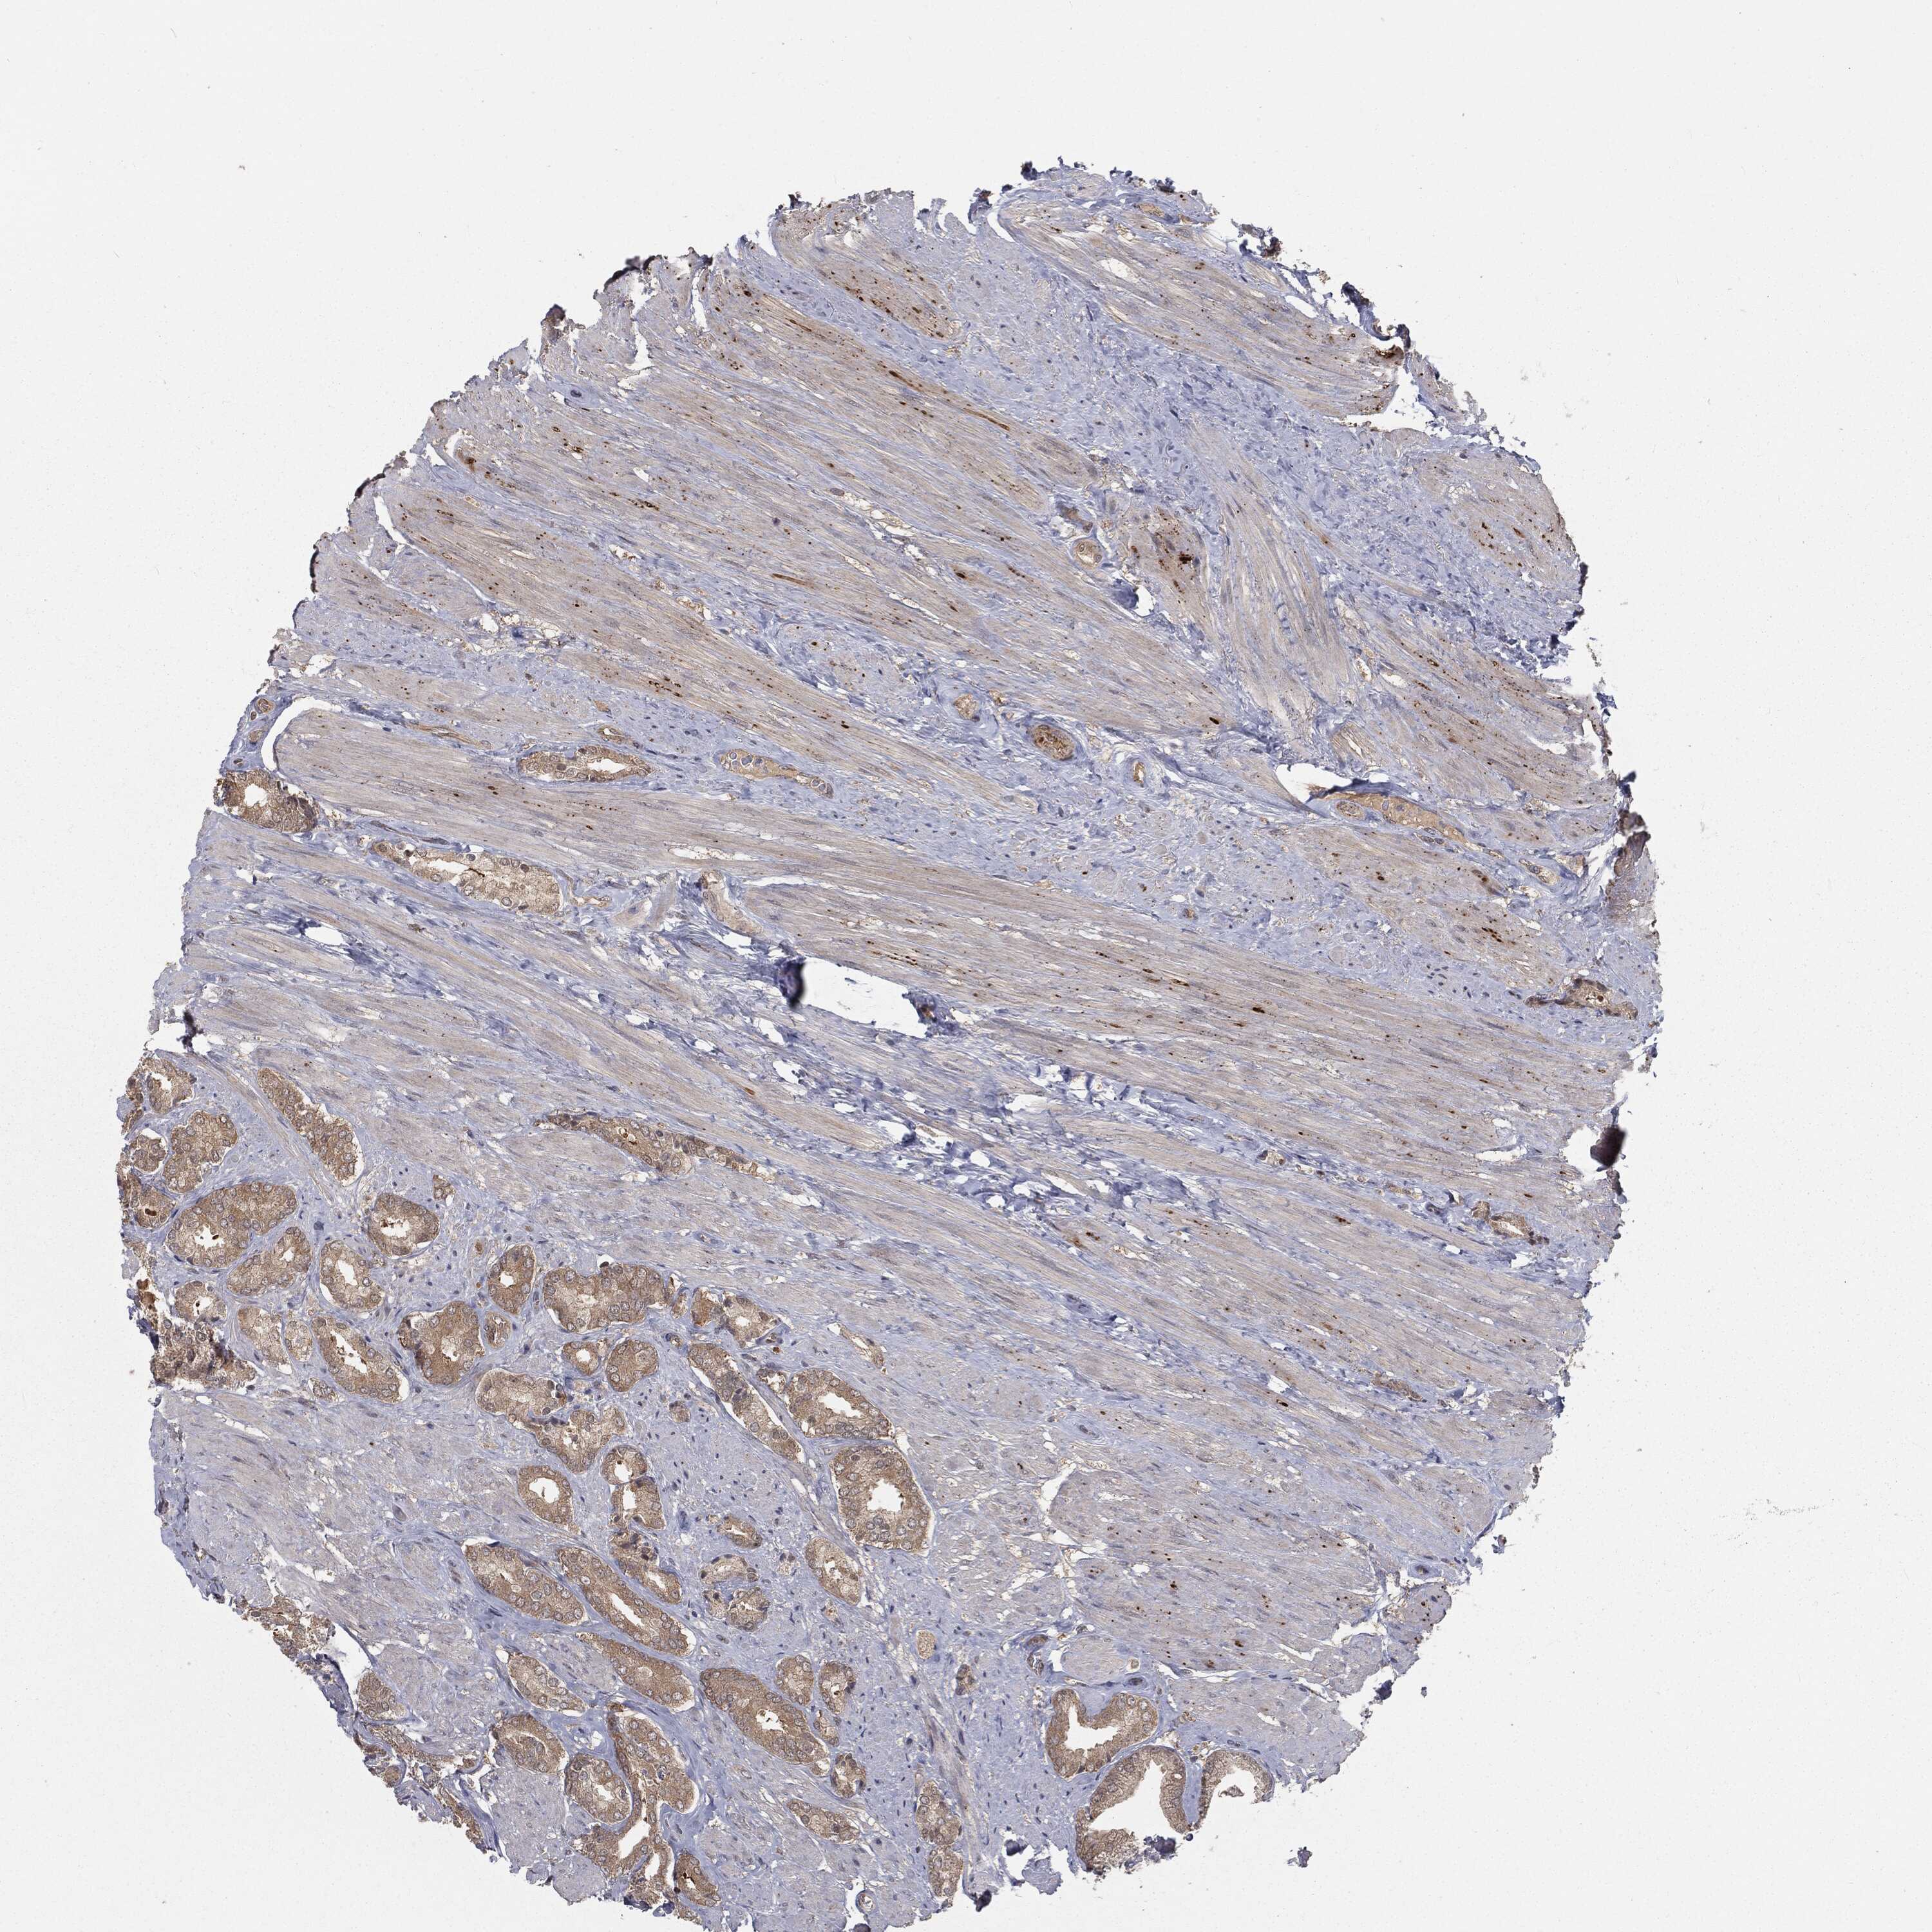

PROSTATE CANCER - Protein expressioni

A mouse-over function shows sample information and annotation data. Click on an image to view it in a full screen mode. Samples can be filtered based on level of antibody staining by selecting one or several of the following categories: high, medium, low and not detected. The assay and annotation is described here.

Antibody stainingi

Antibody staining in the annotated cell types in the current human tissue is reported as not detected, low, medium, or high, based on conventional immunohistochemistry profiling in selected tissues. This score is based on the combination of the staining intensity and fraction of stained cells.

Each image is clickable and will lead to virtual microscopy that enables deeper exploration of all samples and also displays staining intensity scores, fraction scores and subcellular localization as well as patient and tissue information for each sample.

Antibody HPA032114

Antibody HPA057352

Antibody CAB034296

Staining

High

Medium

Low

Not detected

Intensity

Strong

Moderate

Weak

Negative

Quantity

>75%

75%-25%

<25%

None

Location

Nuclear

Cytoplasmic/membranous

Cytoplasmic/membranous,nuclear

Adenocarcinoma, NOS

Adenocarcinoma, High grade

Adenocarcinoma, Low grade